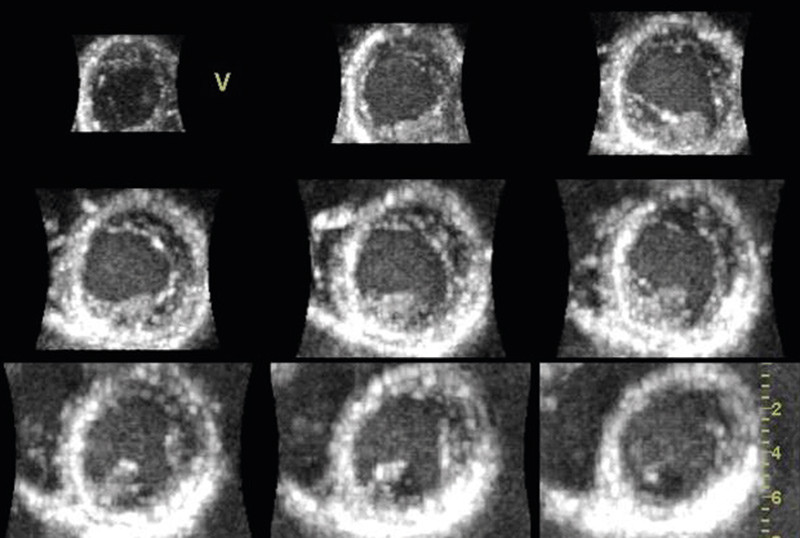

Using 3D echocardiography with full volume recording, the left ventricle can be represented as multiple short-axis images on the screen (Figure 4). In heart muscle diseases such as hypertrophic cardiomyopathy, a better overview can be obtained of where the hypertrophy is distributed. This is particularly useful with more apical variants, as they can be overlooked in routine echocardiography. Some rarer forms of cardiomyopathy, such as non-compaction cardiomyopathy, have characteristic features which can be reproduced easily with 3D echocardiography (Figure 5). However, the additional value of 3D echocardiography in various cardiomyopathies has not as yet been well documented.

Figure 5  Short-axis section of left ventricle in patient with non-compaction cardiomyopathy. In apical sections «spongy»…

Figure 5 Short-axis section of left ventricle in patient with non-compaction cardiomyopathy. In apical sections «spongy» tissue can be observed with prominent crypt formation. In real-time imaging significantly impaired contractions of the ventricle can be seen.